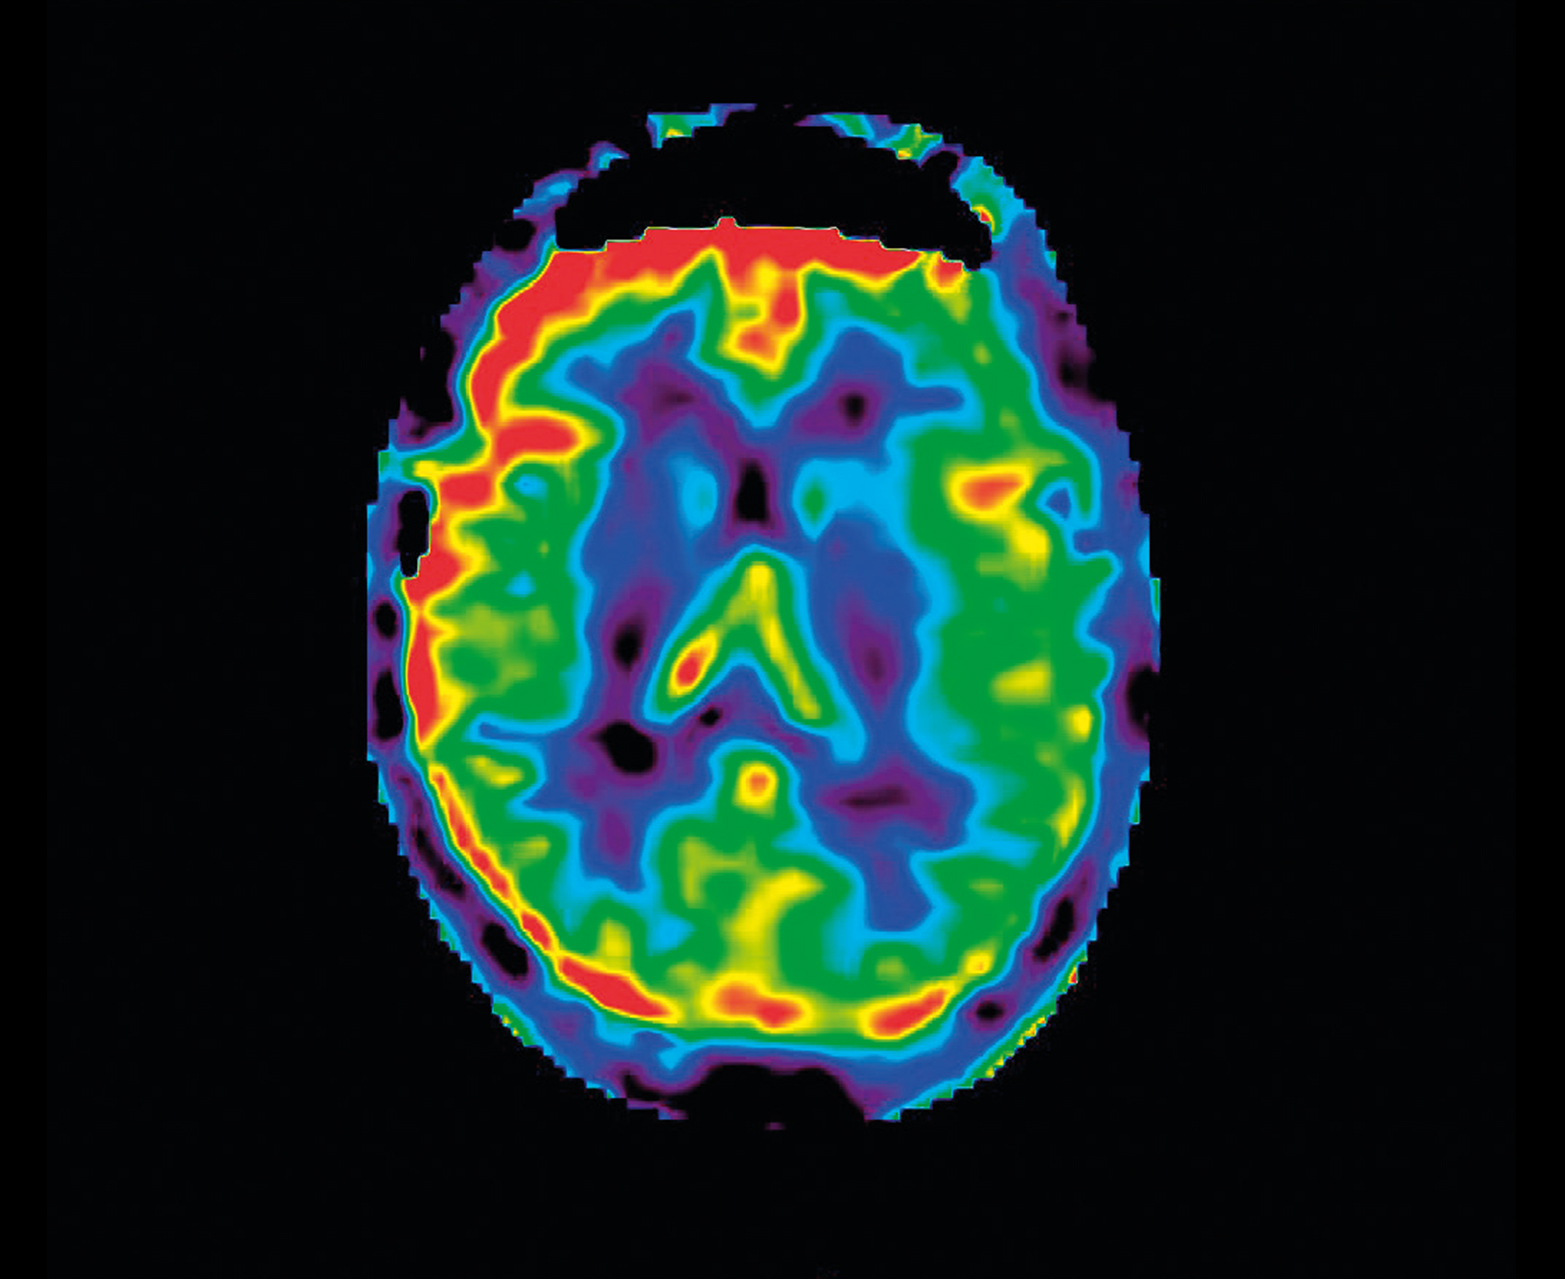

• Неинвазивная перфузия ASL для педиатрии и противопоказания почек

Неконтрастная перфузия ASL